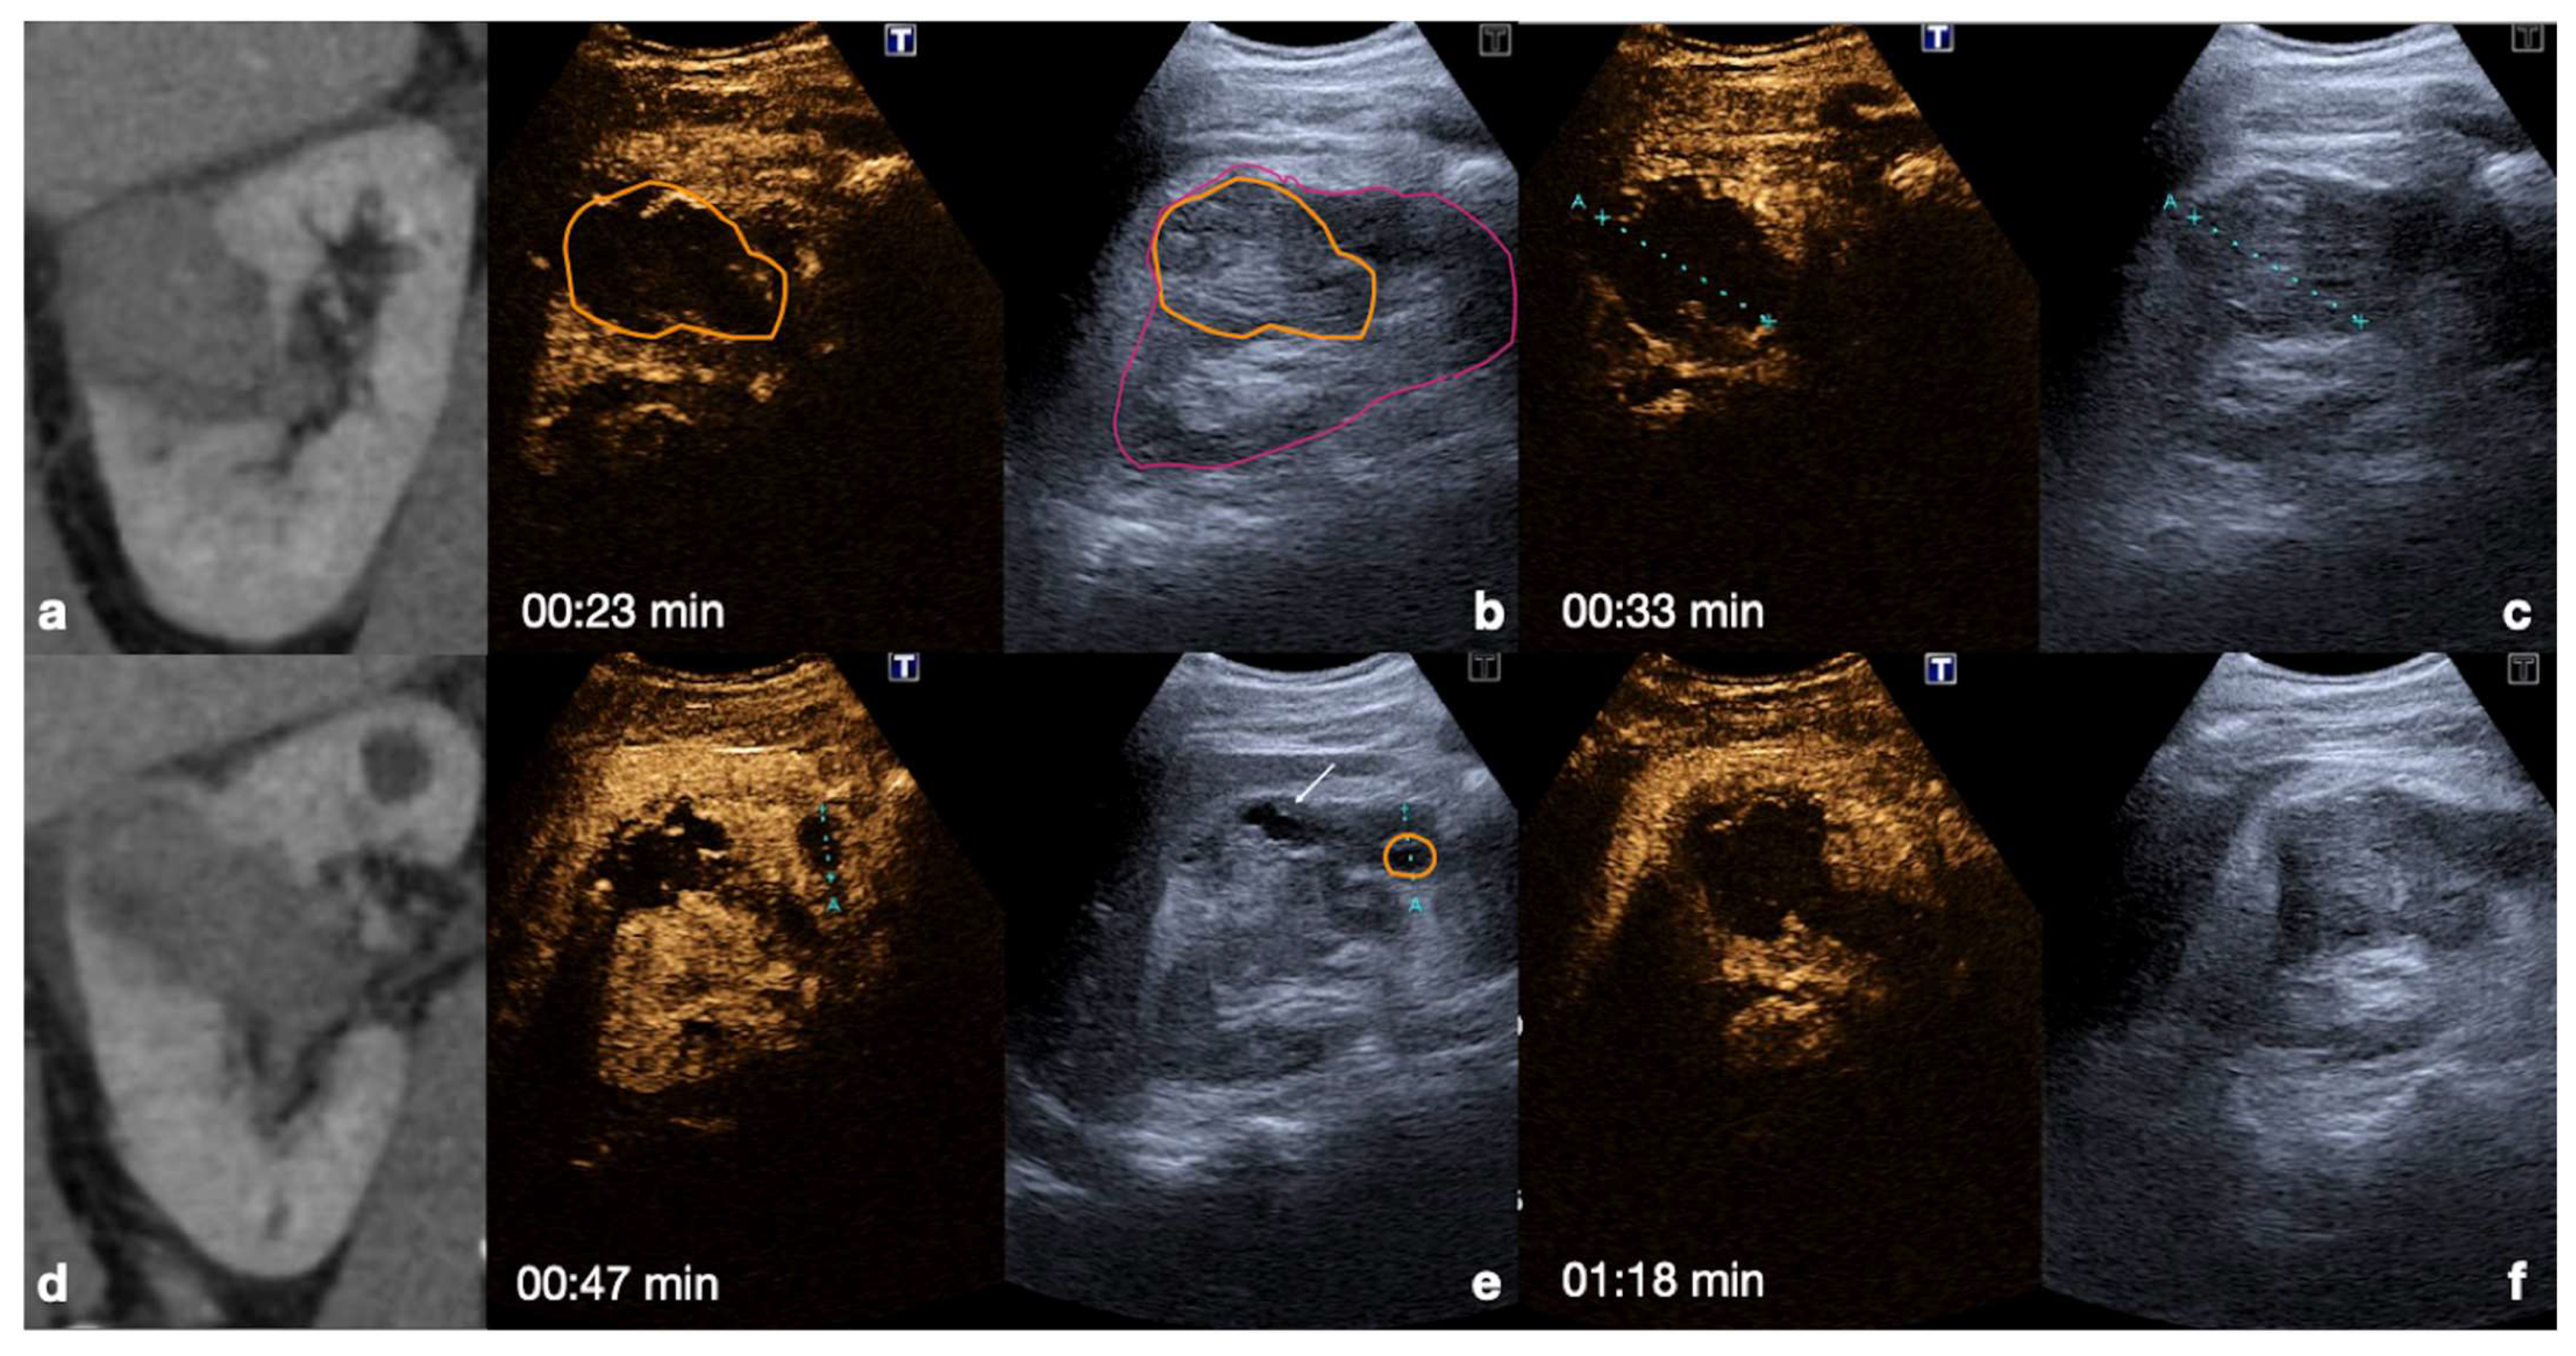

Intraparenchymal haematoma: the haematoma appears as a focal non-enhancing elliptic collection in the parenchyma with poorly defined irregular margins and no internal enhancing vessels. It does not involve interruption of the organ capsule and is particularly evident during the venous phase of the study (Figure 10 and Figure 11) [12,30].

Figure 10.

CT (a,d) and follow-up CEUS (b,c,e,f) of the right kidney in a 57−year-old patient who fell from a height. Follow-up CEUS was performed four days after the admission CT. Note at CEUS the progressive enhancement, at different time points, of the renal cortex in about 30 s (b,c) and the medulla, up to 2.5 min (e,f). The parenchymal hematomas appear as non-enhancing collections (b,e, orange lines) contained in the organ capsule (b, pink lines), without internal enhancing vessel or associated vascular injuries. Due to the physiological evolution of the hematoma, the follow-up, it shows small fluid anechoic areas related to the progressive resorption (e, arrow). Adopted from ref. [30], 2021, Iacobellis, F.; et al.